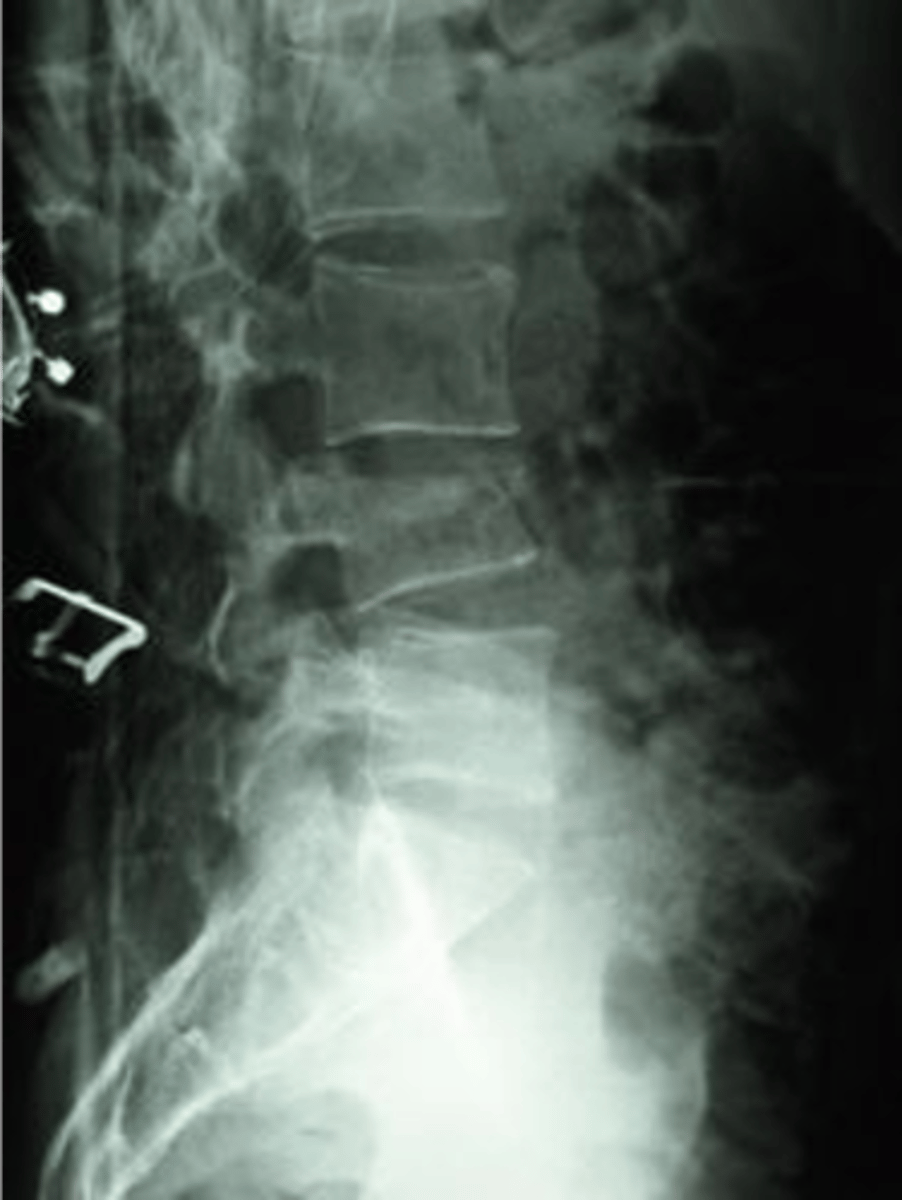

what does this x-ray show

something is wrong with the soft tissue